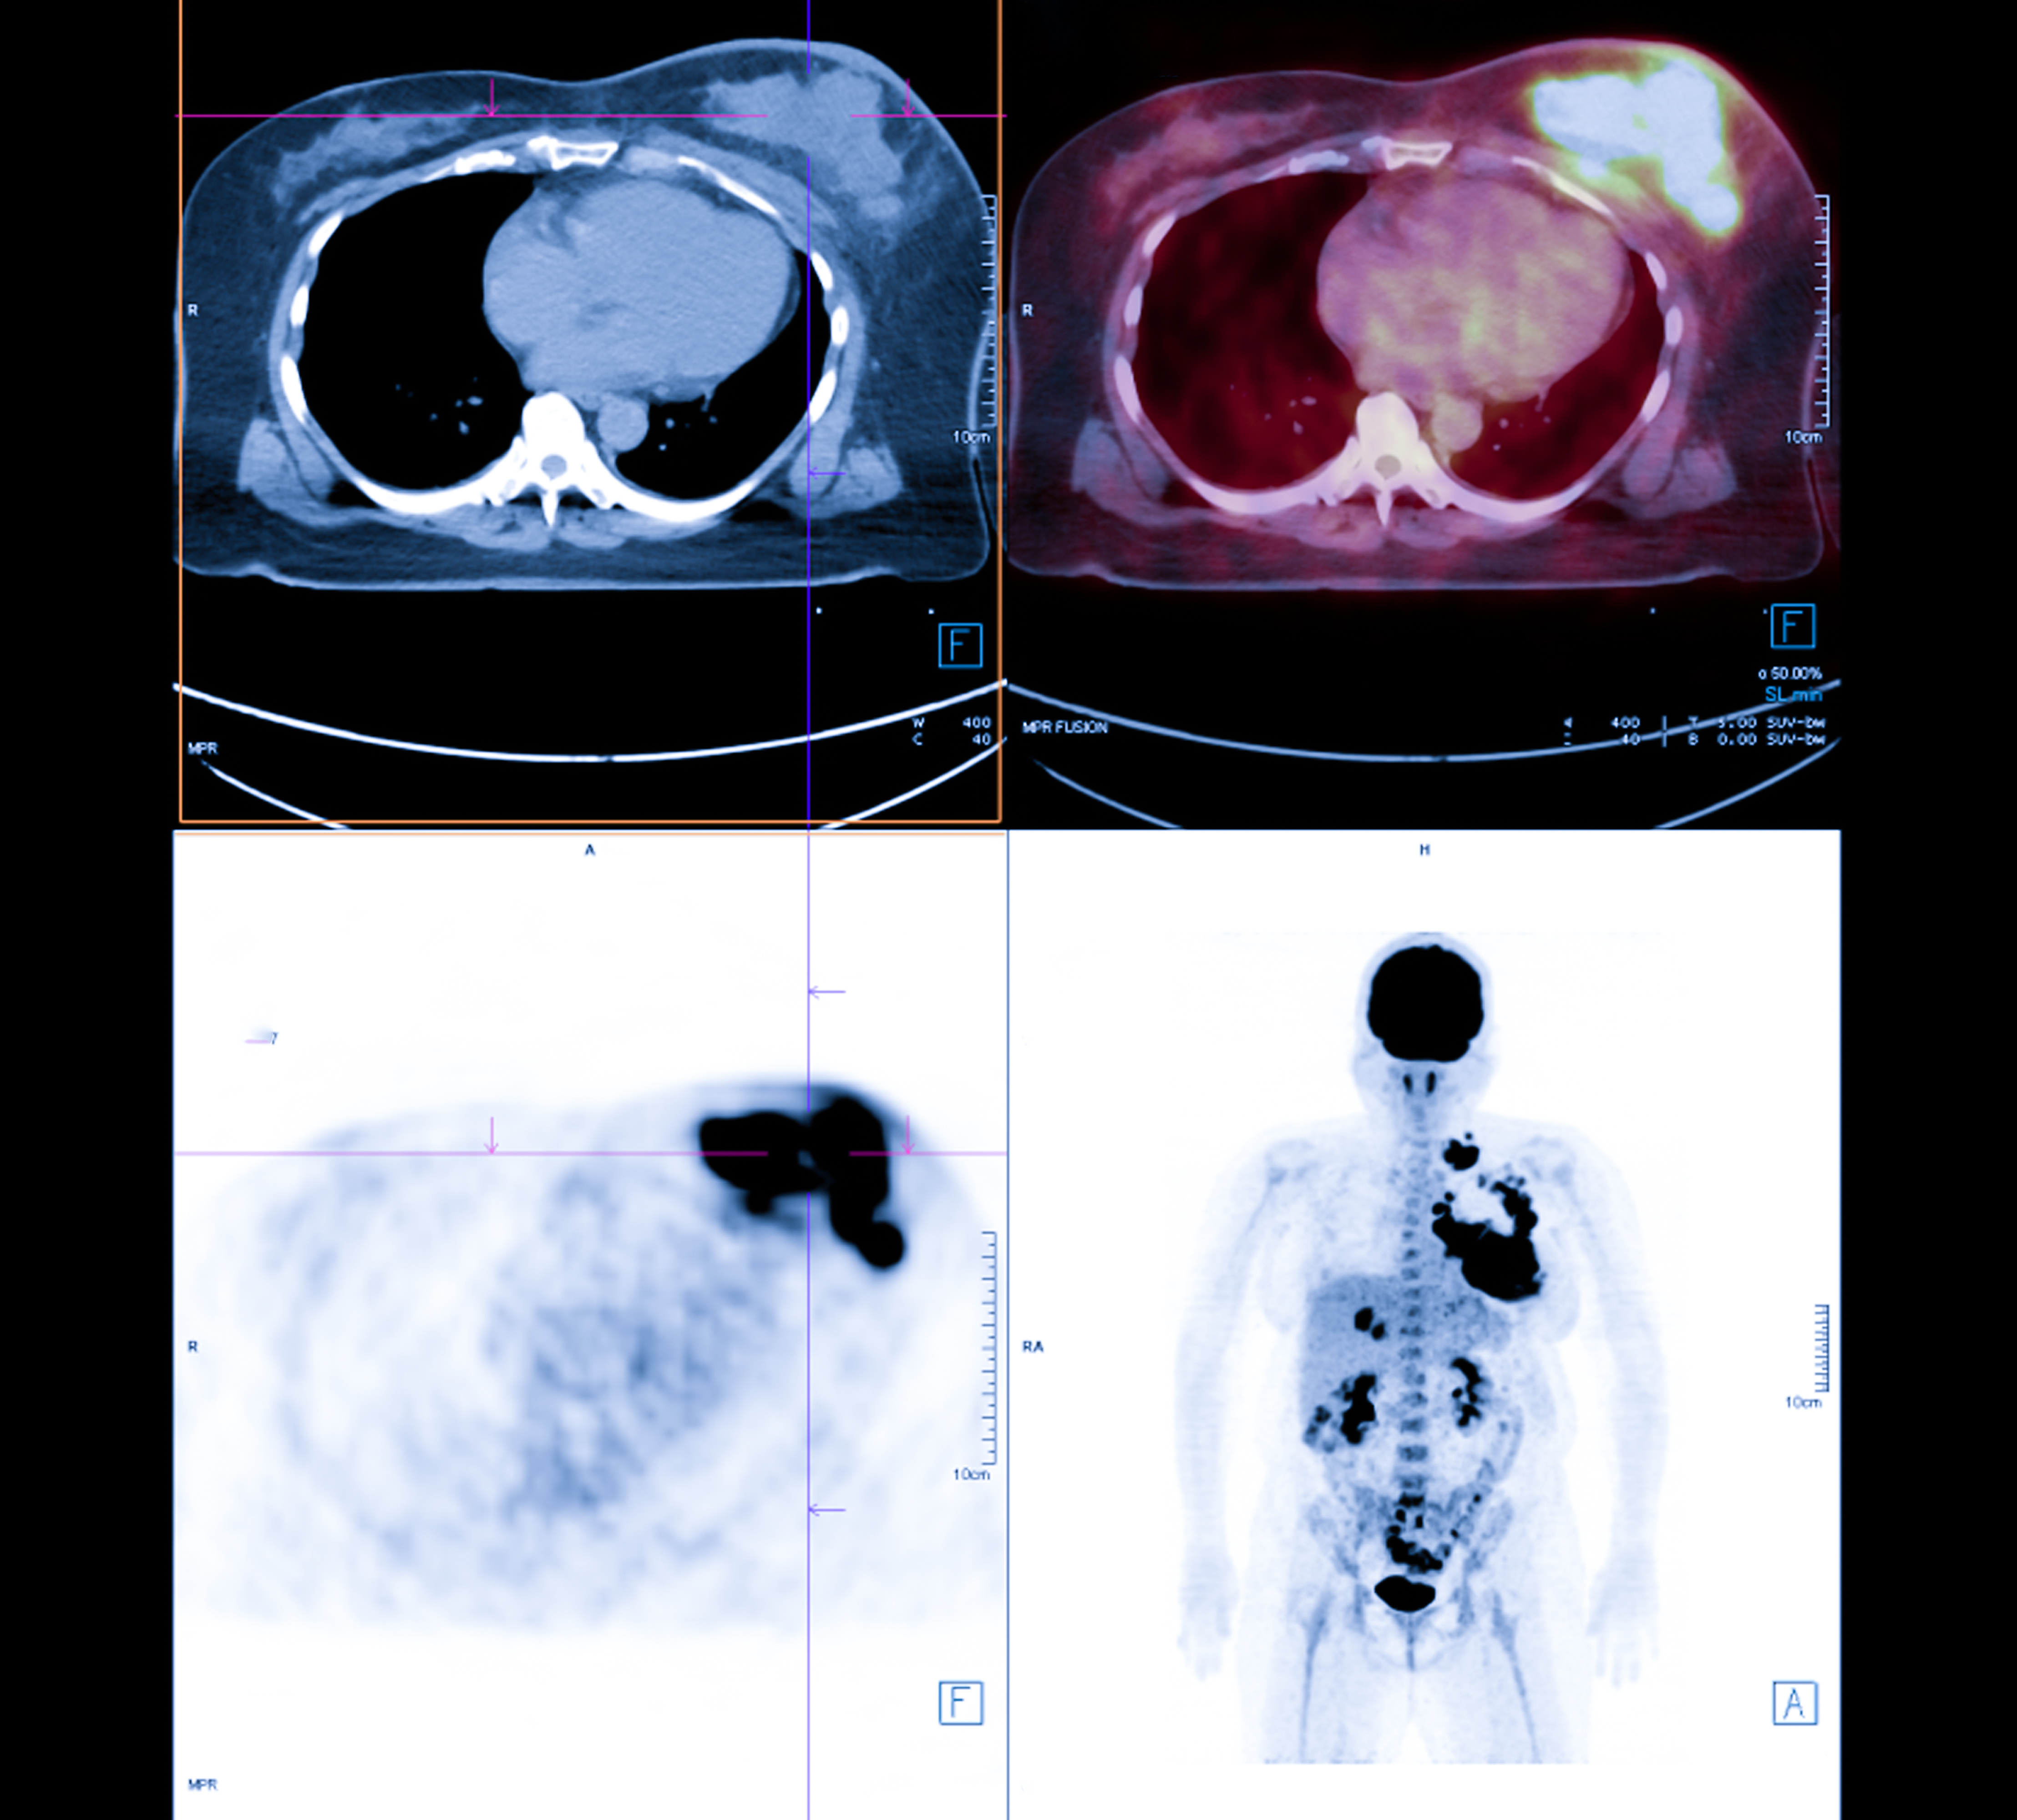

Theranostics consists of using an imaging tracer for in-vivo visualization of a tumor-specific target, which is then addressed by the same or analogous molecule labeled with a therapeutic radionuclide instead of the diagnostic radionuclide.

The approach is already successfully used in neuroendocrine tumor patients and initial PRRT studies show encouraging results with favorable outcomes in patients with treatment-refractory meningioma, the group noted. Yet randomized clinical trials on the efficacy of PRRT in meningiomas are missing and PRRT is not yet approved for meningioma patients by U.S. or European medical agencies, they added.